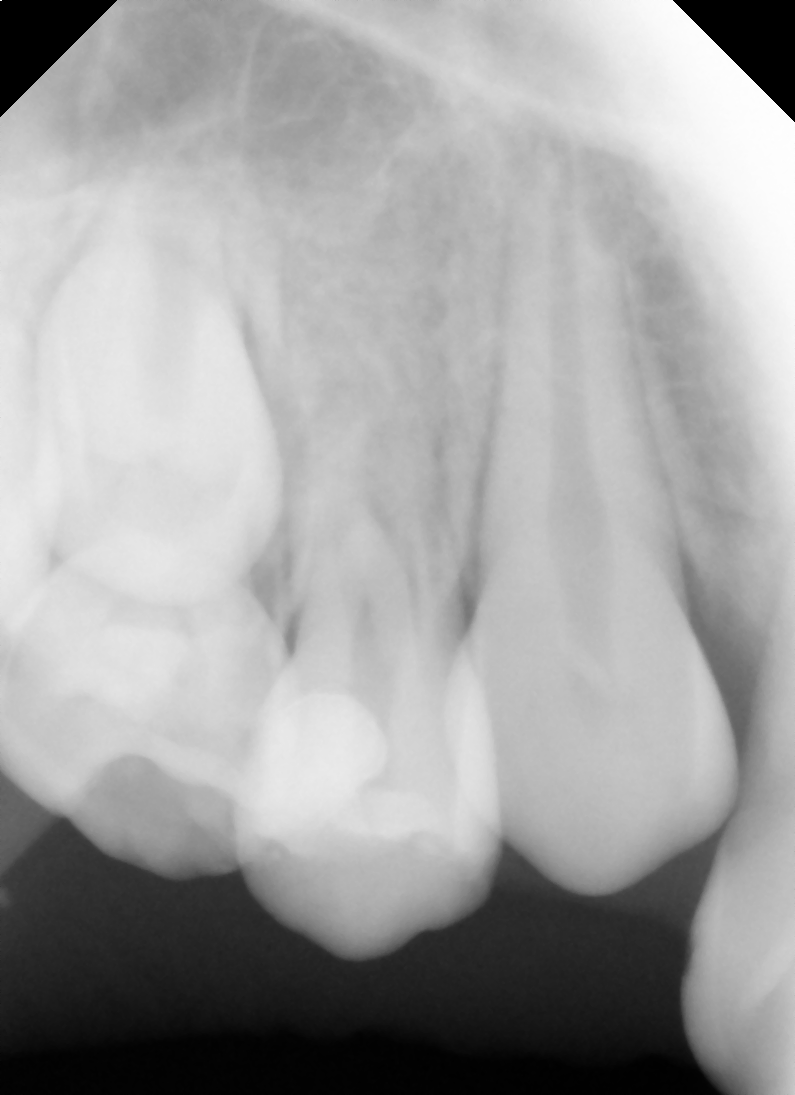

After After

Before Before